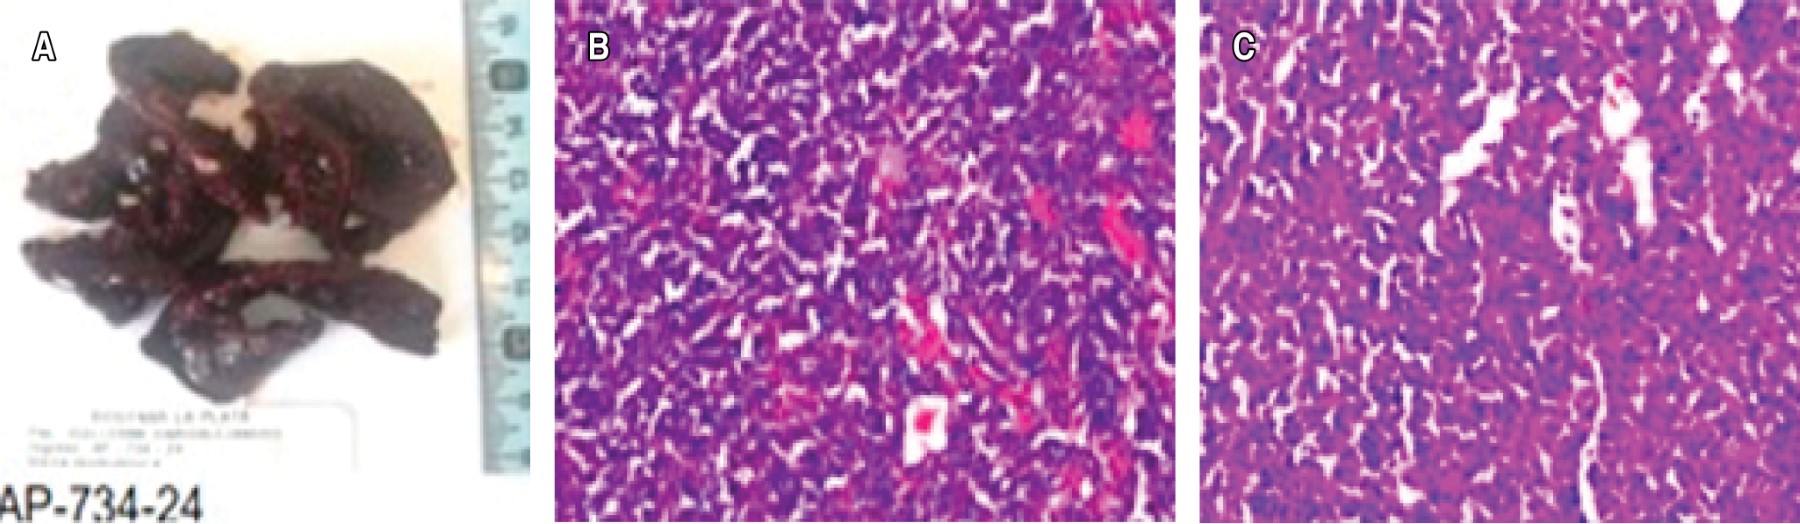

El informe anatomopatológico de la biopsia concluye: examen macroscópico: varios fragmentos irregulares parduzcos de aspecto hemático, blandos, que reunidos mide 7 × 6 cm. Se incluyen en su totalidad (Figura 6A). Examen microscópico: se observa presencia de células de aspecto plasmocitoide, con inmunohistoquímica: kappa positivo, CD38 y CD138 positivo (Figura 6B y 6C).